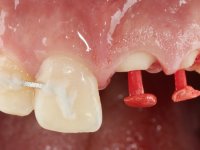

Foi feito o tratamento endodôntico dos dentes 2.1 e 2.2.de imediato, a sintomatologia que o paciente manifestava a isso impunha. Na mesma consulta foi realizada uma extensa gengivetomia com o bisturi elétrico, no sentido de expor os limites cervicais da fratura. Foram colocadas resinas compostas nos remanescentes radiculares com a intenção de reformular a emergência dos tecidos moles. Realizei a impressão dos remanescentes radiculares para confeção em laboratório de uma ponte provisória. A ponte provisória de 2 elementos, apresentava um formato que visava no futuro acomodar o coto dos espigões falsos cotos que iria ser cimentados nos remanescentes radiculares. Apresentava um reforço metálico palatino e dois apoios para os dentes adjacentes, um mesial e outro distal. Os remanescentes radiculares foram preparados para a confeção de dois espigões falso coto fundidos. As linhas de acabamento cervical foram definidas e os canais radiculares desobturados e preparados. A impressão foi realizada com a utilização de tutores de plástico com a técnica de dupla mistura. O afastamento gengival foi feito utilizando pasta de caolino. A ponte provisória foi rebasada em boca com acrílico auto polimerizavel, cimentada provisoriamente sobre as raízes e os apoios colados aos dentes adjacentes. No laboratório foram confecionados os E.F.C. fundidos, tendo o cuidado de preservar espaço para a definição no re preparo dentário da linha de acabamento cervical. Removida a ponte provisória foi feita a cimentação dos E.F.C. fundidos com cimento de ionómero de vidro reforçado com resina. A ponte provisória teve que ser retocada para permitir a acomodação dos cotos e simultaneamente foi readaptada à redefinida linha de acabamento cervical. Durante 2 meses a ponte provisória acompanhou a estabilização periodontal das raízes traumatizadas e simultaneamente conseguiu a maturação da arquitetura gengival.

Durante esse período foi também removida a férula dos dentes 1.3, 1.2 e 1.1 no sentido de avaliar a sua estabilidade. Esta remoção foi feita com muito cuidado para não danificar a superfície vestibular dos dentes. Foram utilizados discos de polimento de forma sequencial e taças de borracha. Após a repetição de testes de vitalidade verificou-se a necrose do dente 1.1, tendo sido realizado o necessário tratamento endodôntico. A impressão definitiva foi feita com a técnica de dupla mistura e o caolino utilizado como afastamento gengival. A ponte provisória foi mais uma vez rebasada. No laboratório, utilizando a tecnologia CAD-CAM, foi feita uma infraestrutura em Zr e posteriormente revestida com cerâmica. Durante este processo sentimos a necessidade de acrescentar resina composta por mesial do dente 2.3 com o objetivo de manter os diâmetros mesio-distais simétricos aos dentes do 1.1 e 1.2. Nesse sentido foi confecionada uma chave de silicone transparente que seria utilizada em boca para orientar esse acrescento. Na porção mesial da superfície palatina do dente 2.1 da ponte foi feita uma pequena cavidade que seria utilizada para colocar uma pequena férula de arame com o objetivo de assegurar a eventual abertura de um diastema. Em boca foi realizado um isolamento relativo e feito o acrescento de resina composta no 2.3 com a ajuda da chave de silicone. A ponte foi cimentada definitivamente com cimento de ionómero de vidro reforçado com resina. Finalmente foi colado uma pequena porção de arame entre a ponte e o dente 1.1.